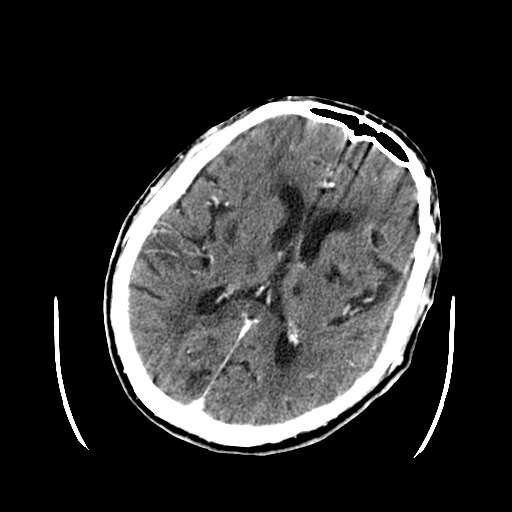

标题: CT10470:M 73Y,颅内占位,请会诊:定位?定性? [打印本页]

m 73

呕吐,意识障碍1小时,伴左侧偏瘫,自诉曾有过左眼视力下降。

病灶区ct值约75hu

考虑:1、中脑右侧、右侧小脑半球、双侧丘脑缺血性脑梗塞;

2、右侧后交通动脉动脉瘤;

3、双侧基底节区腔隙性脑软化灶;

4、脑白质稀疏症。

考虑:1、中脑右侧、右侧小脑半球缺血性脑梗塞;

3、双侧基底节区\\双侧丘脑腔隙性脑软化灶;